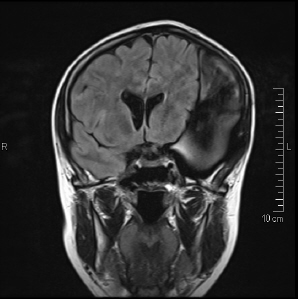

Hatte ja gesagt dass ich heute MRT Termin habe. Ich denke ich stell einfach mal von jeder Perspektiven Serie ein Bild ein und dann könnt ihr Euch selbst eine Meinung bilden ob gut oder schlecht. Einfach auf das Bild klicken, dann seht ihr es etwas größer.

Ich denke es ist nicht so ganz zu übersehen welches hier der schlechte Teil ist in meinem Kopf ist und das meine Hirnmittellinie alles andere als gerade ist. Und dass sich die ganze Sache im Vergleich zu letztem Mal auch noch mal wieder ein Stückchen mehr breit gemacht hat in meinem Kopf brauch ich wohl auch nicht so ganz zu erwähnen.

diese MRT Bilder sind von meinem Kopf. Gehört also mir ganz alleine. Mein Hund hat schwere HD auf beiden Seiten. Aber davon hab ich kein Röntgen oder MRT Biild.